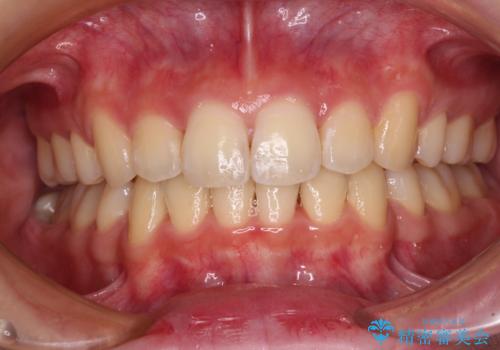

ディープバイトや奥歯の咬み合わせなど、インビザライン矯正では限界がありワイヤー装置での治療に及ばない仕上がりとなりました。

ただし、患者様としては八重歯や、それに伴う唇の閉じにくさが改善されたとのことで、納得いく状態での治療終了となりました。